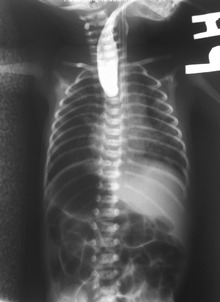

Plain x-ray with contrast in the upper esophagus above the atresia.

On plain X-ray, a feeding tube will not be seen pass through the esophagus and remain coiled in the upper oesophageal pouch.[3]

If any of the above signs/symptoms are noticed, a catheter is gently passed into the esophagus to check for resistance. If resistance is noted, other studies will be done to confirm the diagnosis. A catheter can be inserted and will show up as white on a regular x-ray film to demonstrate the blind pouch ending. Sometimes a small amount of barium (chalk-like liquid) is placed through the mouth to diagnose the problems.